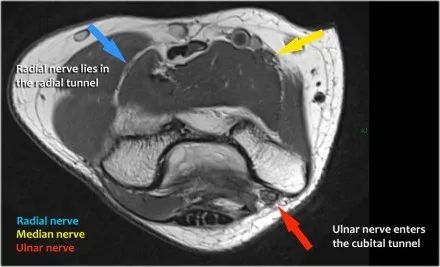

在研究韧带时,尤其是UCL,始终使用轴向图像。如果你看内侧上髁,你会发现后束是一个薄的结构(蓝色箭头)。注意在肘管内的尺神经。

后束形成肘管隧道的地板。支持带覆盖肘管。请注意,前束更厚(白色箭头)。您可以看到前韧带和后韧带之间的区别,即使它们形成一条韧带。走向远端,我们会看到它们合并在一起以附着于崇高的结节。

尺神经:在这里,我们看到了肘管内的尺神经。尺骨侧支带的后带形成隧道的底部,而支持带形成屋顶。

该患者有尺神经神经病变。肘管综合征是一种常见的周围神经病变。它产生于肘管内尺神经,其中该神经传递肘管支持带的下方的压缩。

桡神经:在桡骨头水平可以最好地识别桡神经,在那里你可以看到桡骨隧道中的浅表和深支(箭头)。这是寻找桡神经的非常一致的地方。